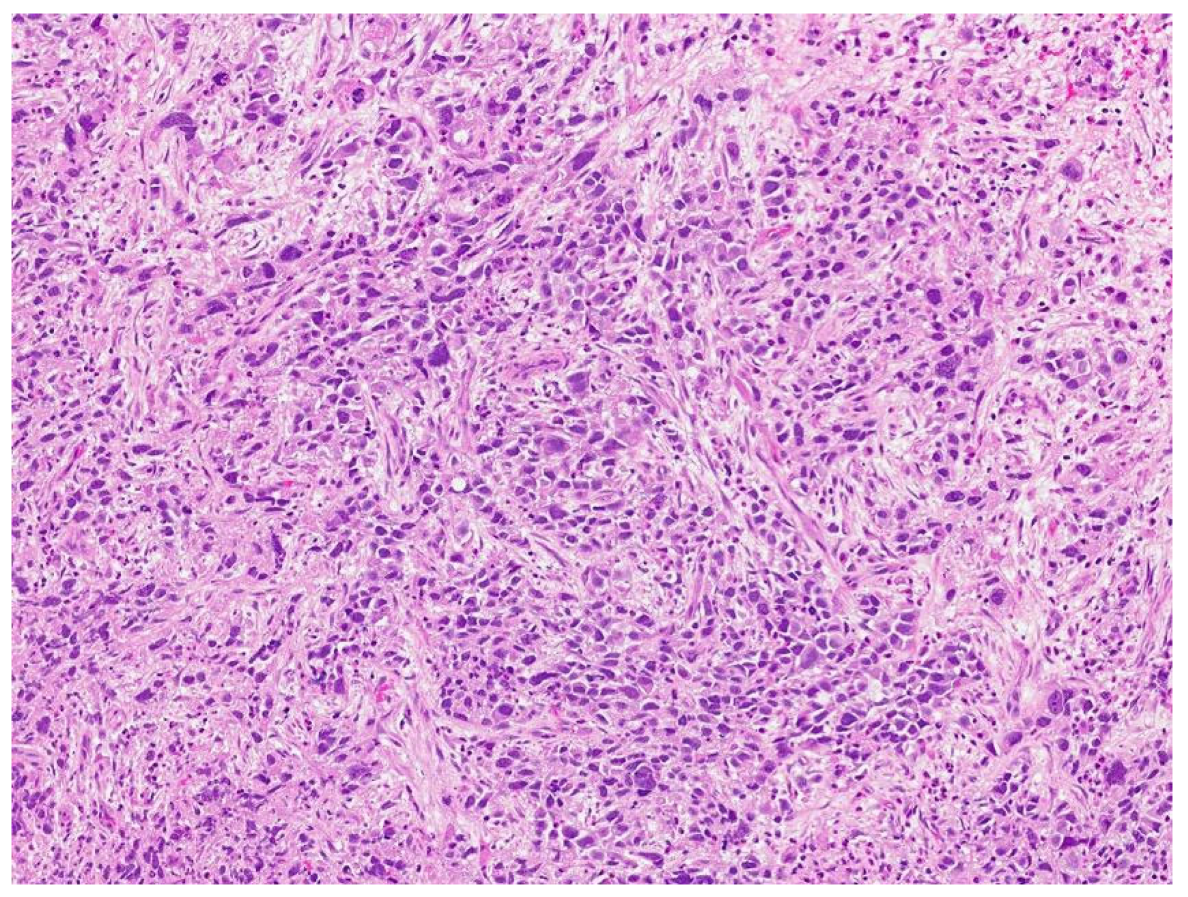

| Patient NSGCT Type | Status | Pathology of Primary | Stage at Time of Diagnosis | S-YSTemic Chemo | Date: Pathology after Chemo |

|---|---|---|---|---|---|

| 1 ETT | Cured | 100% S (elevated AFP) | IIX | BEP x1, VIP x3, paclitaxel (docetaxel), doxorubicin, gemcitabine, | 6/2012: 90% T, 10% ETT + adenocarcinoma |

| 2 S-YST | Cured | 5% E, 90% S, 5% Y | IIIC | BEP x4 | 5/2018, 4/2019, 4/2020: 99% S-YST + 1% T |

| 3 ETT | Cured | 80% ETT, 20% T | IIC | BEP x3 | 1/2018: T w/minute ETT |

| 4 S-YST | Died | NA Y in met | IIIC | BEP x4 | 9/2016: T 1/2021: S-YST |

| 5 ETT | Died | 100% E | IIIA | BEP x1, EP x3, TIP x4, POMB x2, ATP x4, TIP x1/HDC + SCT | 7/2019: Embryonal 11/2019: ETT 1/2020: Choriocarcinoma |

| 6. ETT | Died | 99% E, 1% T | IIIA | BEP x3, TIP x3, ATP | 9/2018: E, C 7/2019, 8/2019: 60% ETT + squamous cell carcinoma |

| 7 S-YST | Died | NA i(12p)+ in met | IIC | BEP x2, XELOX, ATP x2 | 8/2019: S-YST (Unresectable) |